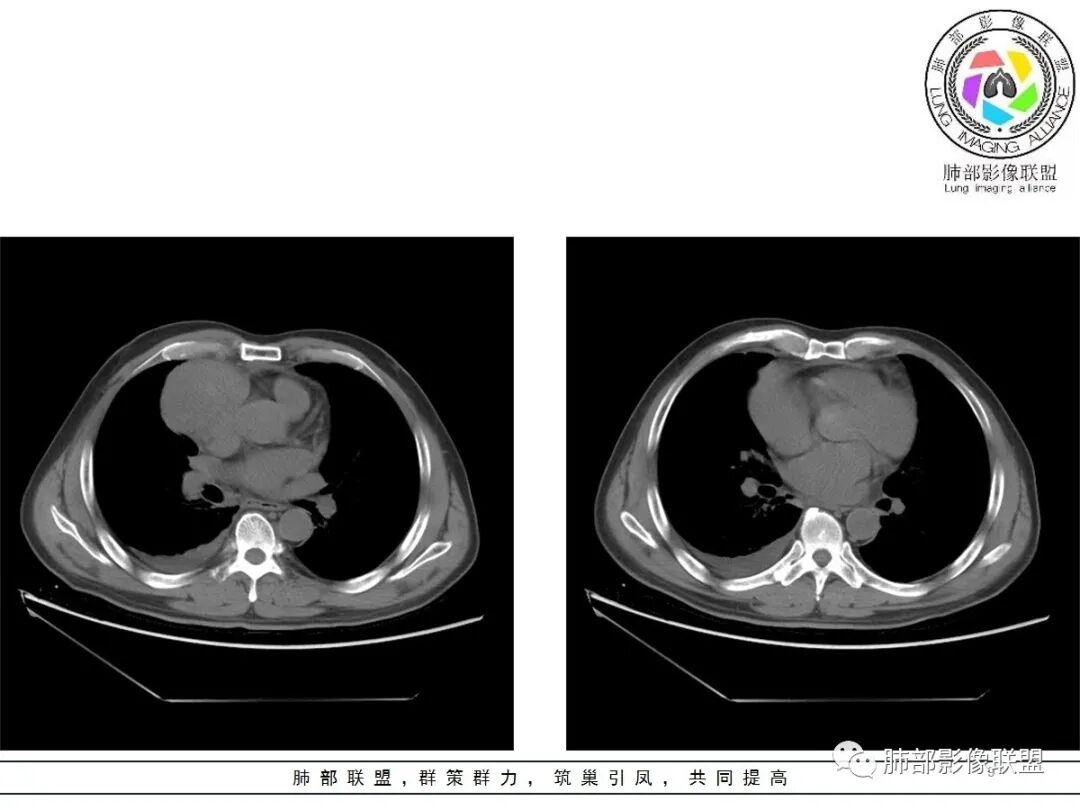

4.四天内病灶变化快,块影增大且不规则,包膜似不完整,边界不清,上份可见浸润或渗出,与周围心脏大血管及心包等间隙不清。胸水增多。

5.未见明显淋巴结增大

第一次的检查符合胸腺瘤影像学改变,短期内的形态学改变及突然出现的边界模糊或浸润等,符合出血或炎症。

结果:符合B型胸腺瘤伴出血,坏死囊性变,局部脓肿形成